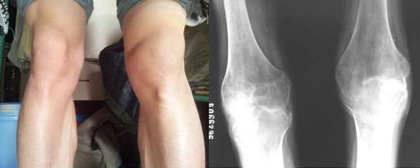

(图:刘先生治疗前的症状表现及ct显示)

来到成都风湿医院后,郭光华主任为刘先生进行系统规范的检查,检查报告显示刘先生C-反应蛋白26.15mg/L,血沉49mm/h,血小板450×10∧9/L,抗CCP抗体150RU/ml(正常参考值〈12RU/ml)。而且刘先生的膝关节开始肿胀,关节间隙狭窄,关节面边缘模糊不清,遭受到严重的破坏,凹凸不平或囊状透亮区,肘关节、膝关节肿胀,膝关节伸不直,脚踝关节活动受限。